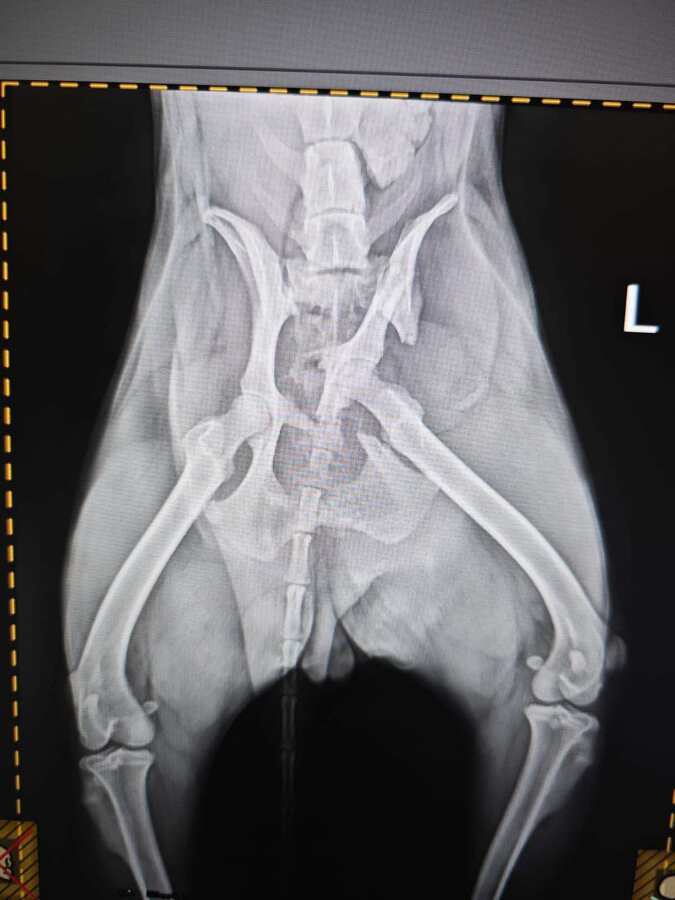

Diese kleine Hündin hatte einen Autounfall und wurde verletzt von den Hundefängern im Tierheim Bucov abgegeben. Nena wurde direkt untersucht und dabei wurde festgestellt, dass ihre linke Hüfte gebrochen ist. Sie wurde umgehend zu Spezialisten in Bukarest gebracht und operiert. Nena ist völlig fertig und unter Schock. Dennoch lässt sie sich vorsichtig anfassen.

hatte Hüft-OP nach Autounfall